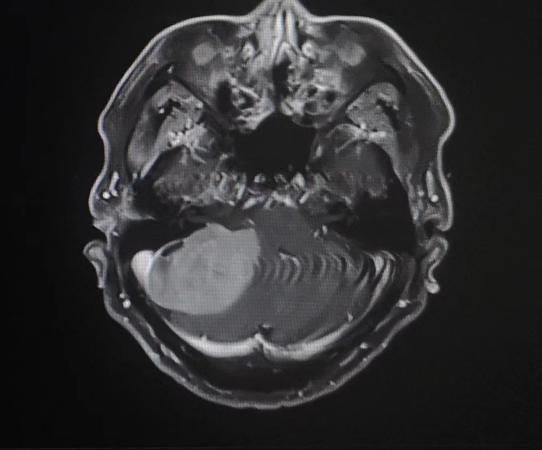

患者入院后,头颅MR检查后发现,小脑右侧长了巨大肿瘤,直径约6公分,患者家属收到不小的惊吓。患者4年前曾做过一次头颅核磁共振,当时肿瘤较小,考虑到患者已经88岁,家人还是决定保守观察,没想到如今,它已经长大到足足有一个土豆那么大,而且患者头晕较重,反复恶心、呕吐,卧床不起,因此必须进行手术,才能解决患者病症。